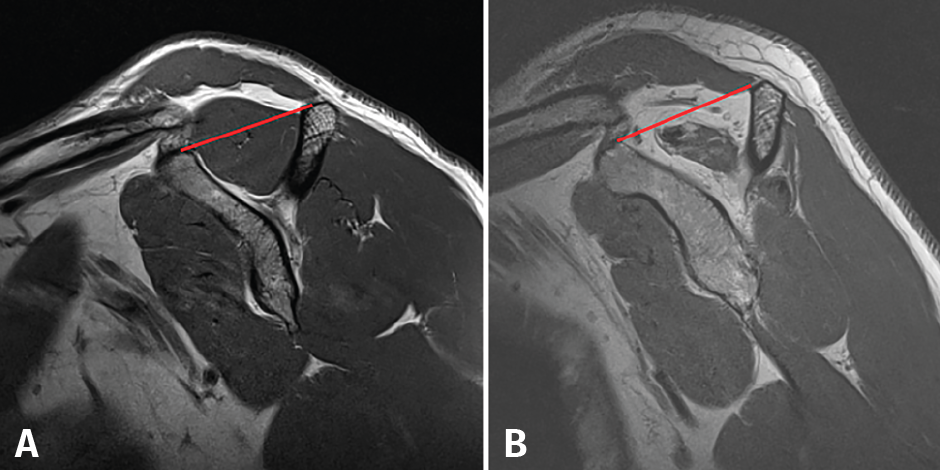

Figura 4. Tangent sign según Zanetti. En condiciones no patológicas, el músculo del supraespinoso sobrepasa una línea trazada desde el margen superior de la coracoides al borde superior de la espina de la escápula (línea roja): A: tangent sign negativo; B: tangent sign positivo.

Otro de los parámetros que nos permite evaluar la RM es la degeneración grasa del músculo(37,38). La pérdida de la tensión que sufre el músculo tras la rotura tendinosa desencadena una serie de cambios fisiopatológicos que llevan a la atrofia radial y longitudinal de la fibra muscular, que con el tiempo progresa hacia la fibrosis y la infiltración grasa(39). Recientemente, se publicó que no existía relación entre la neuropatía del supraescapular, presente en un alto porcentaje de roturas crónicas, y la degeneración grasa(40). La infiltración grasa de los músculos del manguito rotador se ha comprobado como un factor de mal pronóstico para su reparabilidad(35,37,38), por lo que es esencial reconocerla y cuantificarla previamente a la cirugía para planificar el tratamiento de elección. Goutallier en 1994(41) estableció un sistema de clasificación basado en el porcentaje de infiltración grasa que presentaban los músculos del manguito rotador mediante tomografía axial computarizada (TAC) y, posteriormente, Fuchs et al.(42) validaron la clasificación para la RM. Zanetti(43) describió el tangent sign, un signo basado en la RM para valorar la atrofia muscular según el cual el músculo supraespinoso en condiciones normales debe sobrepasar una línea desde el borde superior de la espina de la escápula hasta el margen superior de la coracoides en un plano sagital oblicuo; si existe atrofia, el supraespinoso se mantendrá por debajo de dicha línea (Figura 4). Este signo está relacionado con la infiltración grasa(44) y está considerado un buen predictor de la reparabilidad del manguito y su viabilidad(45). Finalmente, Thomazeau(46) describió la ratio de ocupación. Utilizando el mismo plano que Zanetti, calcula la relación entre el área que ocupa el supraespinoso y el área total de la fosa supraespinosa (Figura 5). Una relación inferior al 60% nos indica atrofia muscular. Posteriormente, demostró la correlación entre la atrofia del supraespinoso y el tamaño de la rotura, concluyendo que este signo representaba un factor de mal pronóstico para la rerrotura postoperatoria(47).